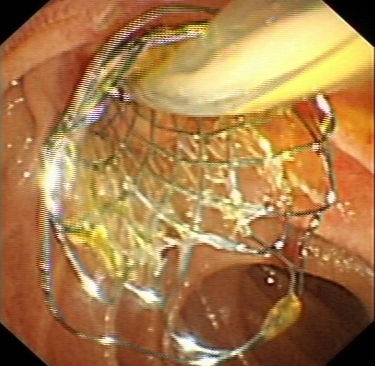

bc72d6558d394d8ea787e762f054a7c5.Jpeg74bcac877ae44a9da8e58dab53d178ee.Jpeg75e90c629e6545de9ee764d5e15bc91e.JpegERCP取出膽總管結(jié)石

對(duì)于無(wú)法手術(shù)切除的膽管或胰腺惡性腫瘤導(dǎo)致的梗阻性黃疸,可以進(jìn)行ERCP下膽道支架植入,以緩解梗阻性黃疸癥狀,提高患者生活質(zhì)量。通過(guò)光動(dòng)力、射頻消融等治療,還可以控制腫瘤的生長(zhǎng),提高膽道支架的通暢期,延長(zhǎng)患者生存時(shí)間。